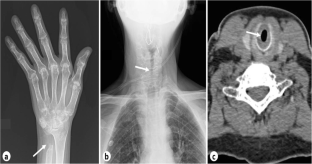

Fig. 1